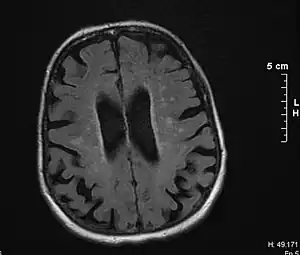

| Brain atrophy on MRI from vascular dementia | |